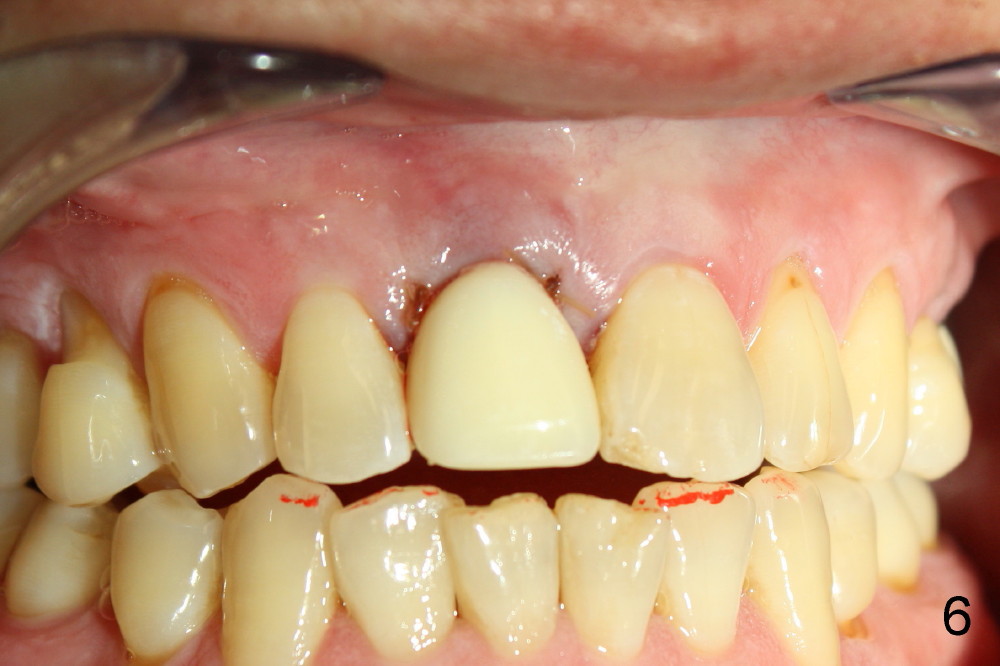

A 55-year-old man has severe pain on the upper right central incisor (Fig.1 *) after biting on a piece of bone. PA confirms crown fracture (Fig.2 <), extending subgingivally (Fig.3 >>). Osteotomy forms using a 2 mm pilot drill and 2.5-3.5 mm reamers (Fig.4). A 5x17 mm Tatum tapered implant is placed, autogenous bone placed in the buccal gap, sutures placed for wound approximation and 3.5 mm 20º angled abutment installed (Fig.5). An immediate provsional is fabricated (Fig.6), cemented and splinted (Fig.7).,

The provisional is dislodged 3.5 months postop; there is no labial atrophy (Fig.8 black arrowhead). The permanent crown (Fig.9 C) is harmonious with the papillae (*). When the try in crown is removed, the gingival tissue looks healthy (Fig.10 *).